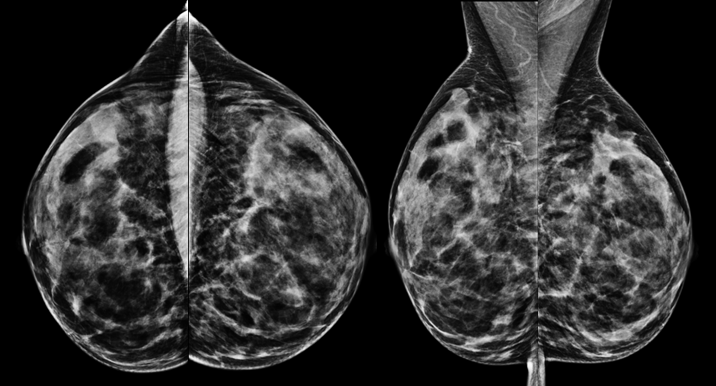

Kernspinuntersuchung einer 55jährigen Patientin mit gesichertem Karzinom in der linken Brust (im Bild rechts, Pfeil)

Die Kernspinuntersuchung der Brust ist nicht generell für die alleinige Brustkrebsfrüherkennung geeignet und kann auch nicht die Mammographie oder die Sonographie ersetzen.